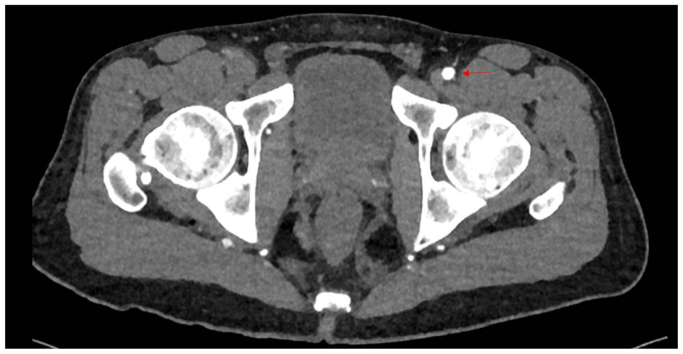

Clinical examination revealed non-palpable dorsalis pedis and posterior tibial pulses bilaterally. The lower extremities were warm, without sensory or motor deficits or evidence of tissue loss. Vascular studies demonstrated an ankle-brachial index of 0.36 on the right and 0.45 on the left. Subsequent workup including a computed tomographic angiography, and arterial duplex imaging revealed occlusion of the right common femoral and distal right superficial femoral arteries with reconstitution of tibial vessels. (Figs 1 and 2). The left lower extremity demonstrated a similar pattern of disease without the common femoral artery occlusion. Extensive workup of other possible etiologies for peripheral vascular disease, including hereditary thrombophilias and other vasculitic syndromes, was negative. Labs were notable for normal immunologic and inflammatory markers, a hemoglobin A1C of 5.7, and a normal lipid panel.

It is unclear if cannabis arteritis represents a subtype of TAO or a distinct clinical entity due to the predominance of concurrent tobacco and cannabis use in as many as 97% of cases reported in the literature.ref. bib2 Furthermore, many recorded substance use histories lack the detail necessary to identify other contributing sources of tobacco exposure, such as the cured tobacco leaves used in blunt wraps.ref. bib4 This case represents a rare instance in which there is minimal exposure to tobacco in both smoking history and “cross-contamination” of cannabis. This patient presented with extensive proximal lesions to the common and superficial femoral arteries and claudication without ischemic ulcerations, which is quite unusual for TAO and may better characterize the unique features of cannabis arteritis.ref. bib6,ref. bib11 To the authors’ knowledge, this also appears to be one of the first case reports linking THC vaping to cannabis arteritis.